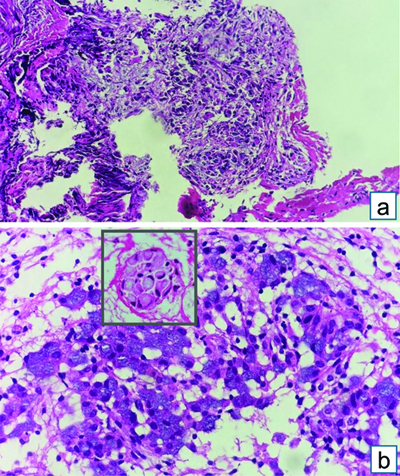

Computed Tomography Pulmonary Angiography (CTPA) was done to rule out pulmonary thromboembolism as the patient continued to be hypoxic and had developed haemoptysis and persistent tachycardia, requiring oxygen therapy. CTPA showed right lower lobe loculated effusion, for which thoracocentesis was attempted with only a dry tap. This was followed-up with the medical thoracoscopic procedure which revealed multiple nodules over the costal surface of the pleura and diaphragm with dense adhesions. Partial adhesiolysis was done and multiple pleural biopsies were taken, which were positive for malignancy, suggestive of adenocarcinoma with SRC morphology [Table/Fig-9].

Pleural biopsy: (a) Fibrocollagenous tissue with infiltration by nests and vague glands of tumour cells (H&E stain x100); (b) Vague glands (inset) nest of tumour cells exhibiting intracellular mucin simulating Signet Ring Cells (SRC) (H&E stain 10x) (Inset-H&E stain 40x).